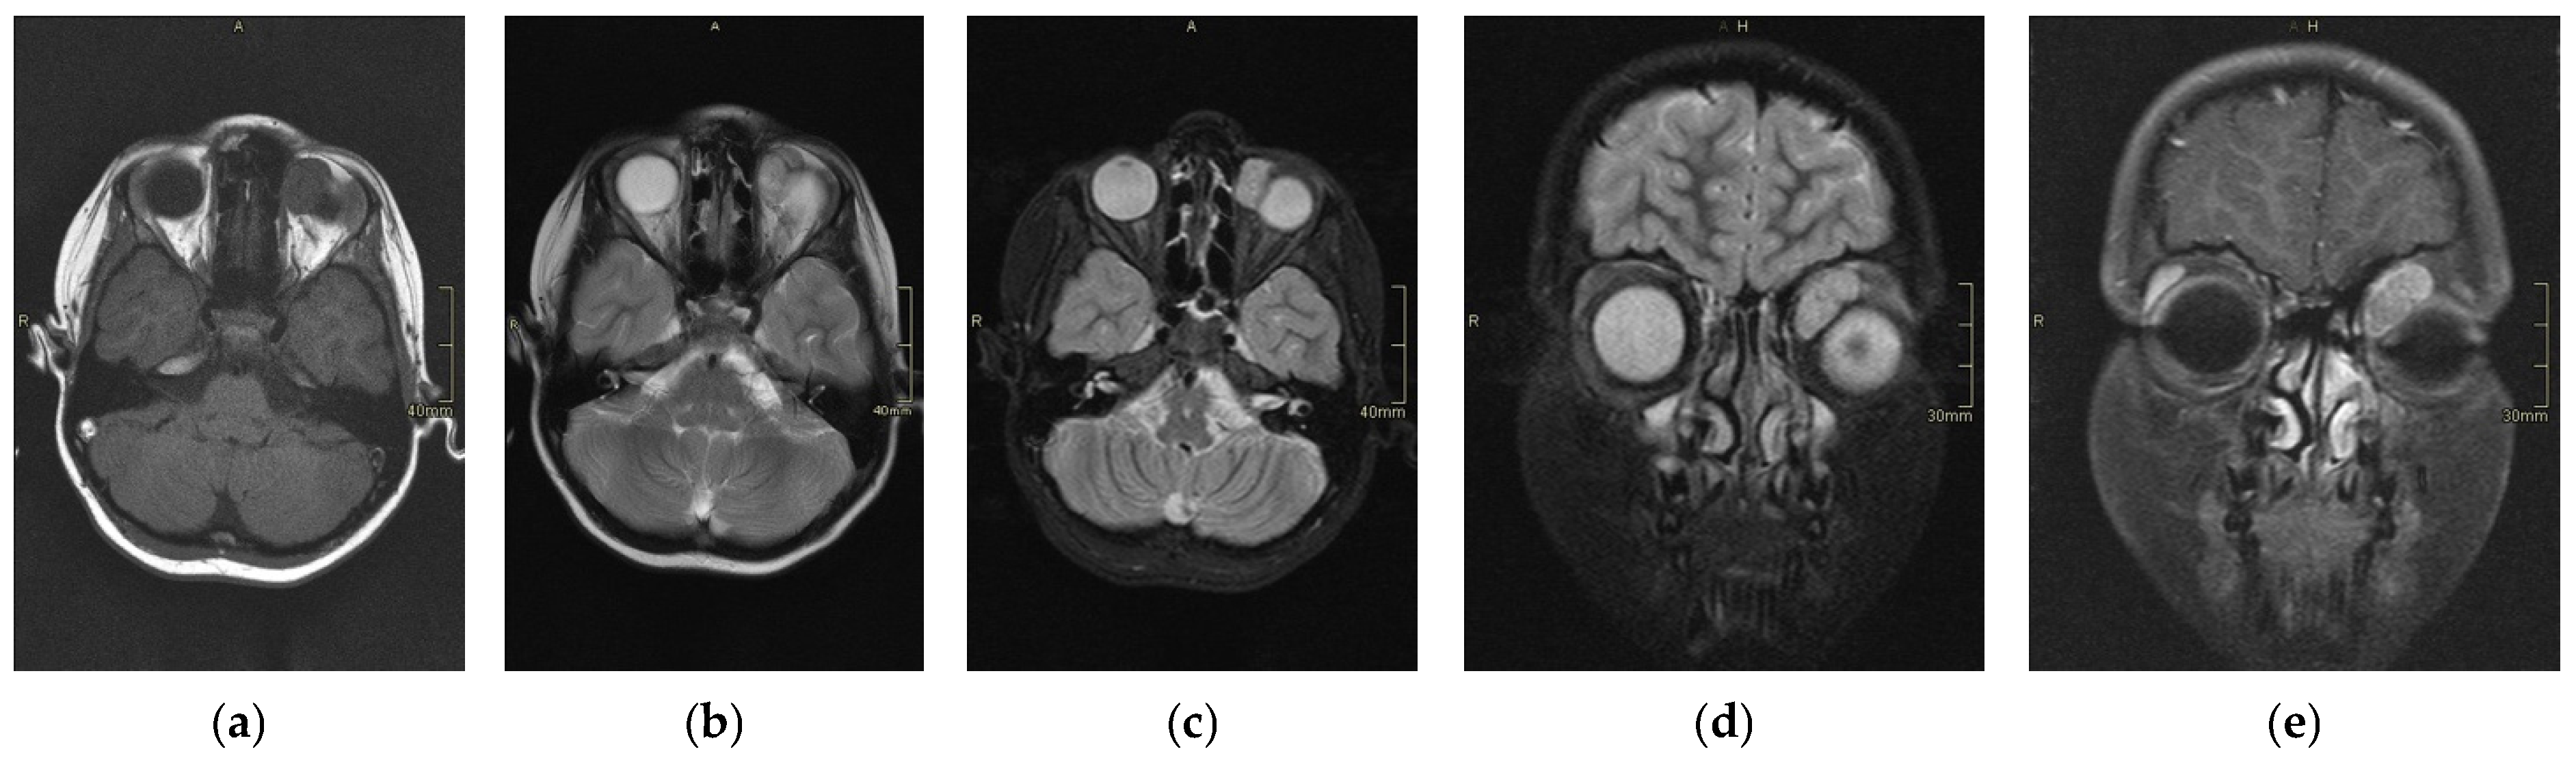

The scans at diagnosis showed masses with hypodense contrast enhancement of the tumor in all cases, with a pattern of generalized enhancement (see Figure 1). MRI at diagnosis showed low signal (isointense or hypointense) of soft tissues on T1-weighted images and high signal (hyperintense) on T2-weighted images, and gadolinium enhancement in all cases (see Figure 2). The tumor border was smooth (in 77% of cases), lobulated (10%), or mixed (13%) (see Figure 3). No association was found between tumor border type and recurrence rate or death.

Figure 1. Computed scan tomography (CT) of orbital RMS case: non contrast axial section (a), contrast axial section (b), and contrast coronal section (c). This case shows a hypodense lesion on CT with post-contrast enhancement.